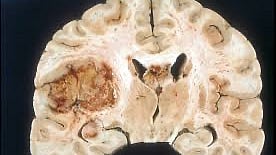

Glioblastoma is a highly aggressive brain tumor, with no cure currently available. While treatments like surgery, radiation, and chemotherapy can extend life expectancy, the prognosis remains grim. Half of the patients die within a year of diagnosis. One of the key challenges in treating glioblastoma is the blood-brain barrier, which limits the efficacy of many cancer drugs by preventing them from reaching the brain.